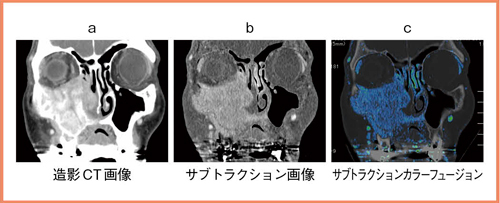

さらに,研究用のBone Subtraction Softwareでは,サブトラクションしたい部位を選択することで,該当部に対し非線形の位置合わせを行い,サブトラクション精度を向上させることができる。作成したデータは,多方向のMPR画像を作ったり,カラーフュージョンさせることも,コンソール上で容易に可能である。

造影CTによる通常の軟部条件のみでは,中頭蓋底の骨破壊は明らかではないが,中頭蓋底の硬膜の肥厚が疑われる(図1a)。サブトラクション画像(図1c)では,MRIにおける脂肪抑制併用造影T1強調像のような画像が得られ,腫瘍が頭蓋底の骨髄を介して硬膜にまで達していることが観察できる。さらに,カラーフュージョン(図1d)することで,視覚的により明瞭な画像が得られる。

通常のCT画像では,上顎洞の後壁が大きく破壊されておらず,翼口蓋窩もおおむね保たれており,上顎全摘手術の適応と思われた(図2a)。しかし,サブトラクション画像では,右翼状突起の基部から斜台まで腫瘍の進展が描出された(図2c)。MRIでも同様の画像所見を示し,手術非適応の診断で重粒子線治療が選択されている。このように,サブトラクション画像をルーチンのCT検査に追加した画像情報として活用することで,がんの頭蓋底骨組織に対しより正確な浸潤評価が可能で,最適な治療方針決定に寄与できる可能性がある。また,ボリュームデータのため,冠状断など任意の断面での再構成画像を簡単に作成することができる点も有益である(図3)。